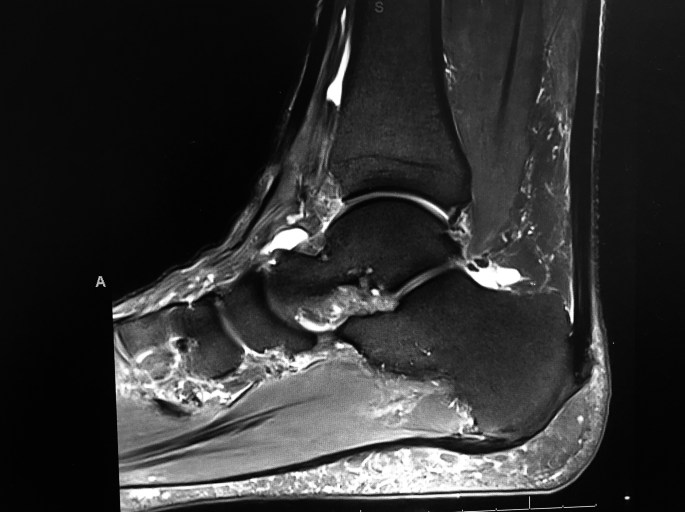

This is a Sagittal MRI of a painful heel, Left foot.